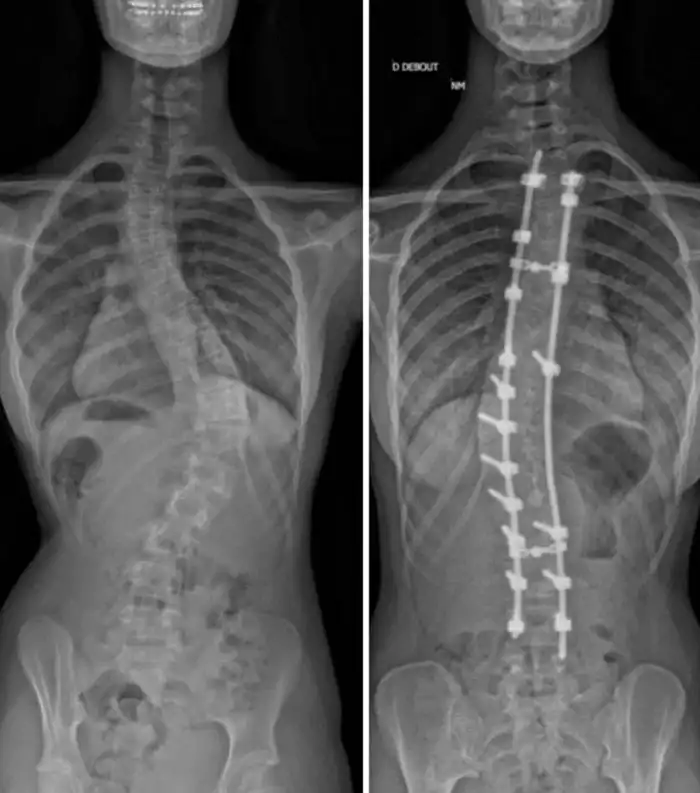

До и После операции на позвоночнике - разница 6 лет